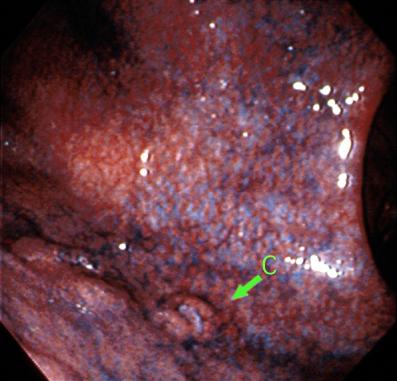

A case of T-cell leukemia with multiple lesions in the stomach

Malignant Lymphoma/ATL(Adult T-cell Leukemia / Lymphoma)

Stomach/Body

Endoscopy

Type 0/IIa (IIa+IIc) Superficial elevated and depressed type

20 - 24

submucosa

Synchronous

Syncronous